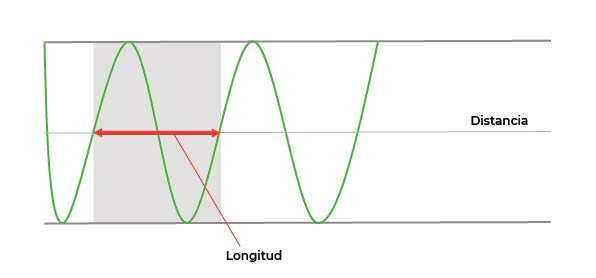

Longitud

La longitud de onda será la distancia que esa onda (se representa por la letra λ) recorre en cada uno de sus ciclos: